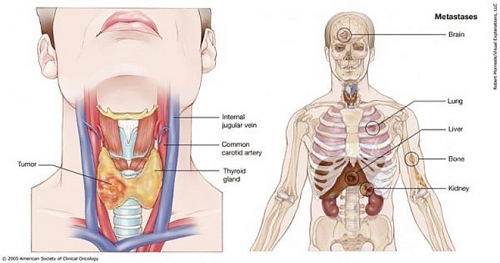

Ung thư tuyến giáp giai đoạn đầu sống được bao lâu?

Ung thư tuyến giáp giai đoạn đầu sống được bao lâu là thắc mắc của nhiều người khi nhận tin mình mắc bệnh. Giải đáp ngay trong bài viết sau!

Triệu chứng ung thư tuyến giáp giai đoạn đầu

Những triệu chứng ung thư tuyến giáp giai đoạn đầu là gì và cần làm thế nào để phòng tránh ung thư tuyến giáp?

Dấu hiệu ung thư tuyến giáp giai đoạn cuối

Dấu hiệu ung thư tuyến giáp giai đoạn cuối bao gồm những gì? Liệu có cách chữa trị nào khi đã tới ung thư tuyến giáp giai đoạn cuối?

Triệu chứng u tuyến giáp ác tính

Triệu chứng u tuyến giáp ác tính bao gồm những gì? U tuyến giáp ác tính có thể chữa dứt điểm khỏi bệnh hay không?

Biểu hiện ung thư tuyến giáp

Biểu hiện ung thư tuyến giáp là gì? Ung thư tuyến giáp có nguy hiểm chết người hay không?